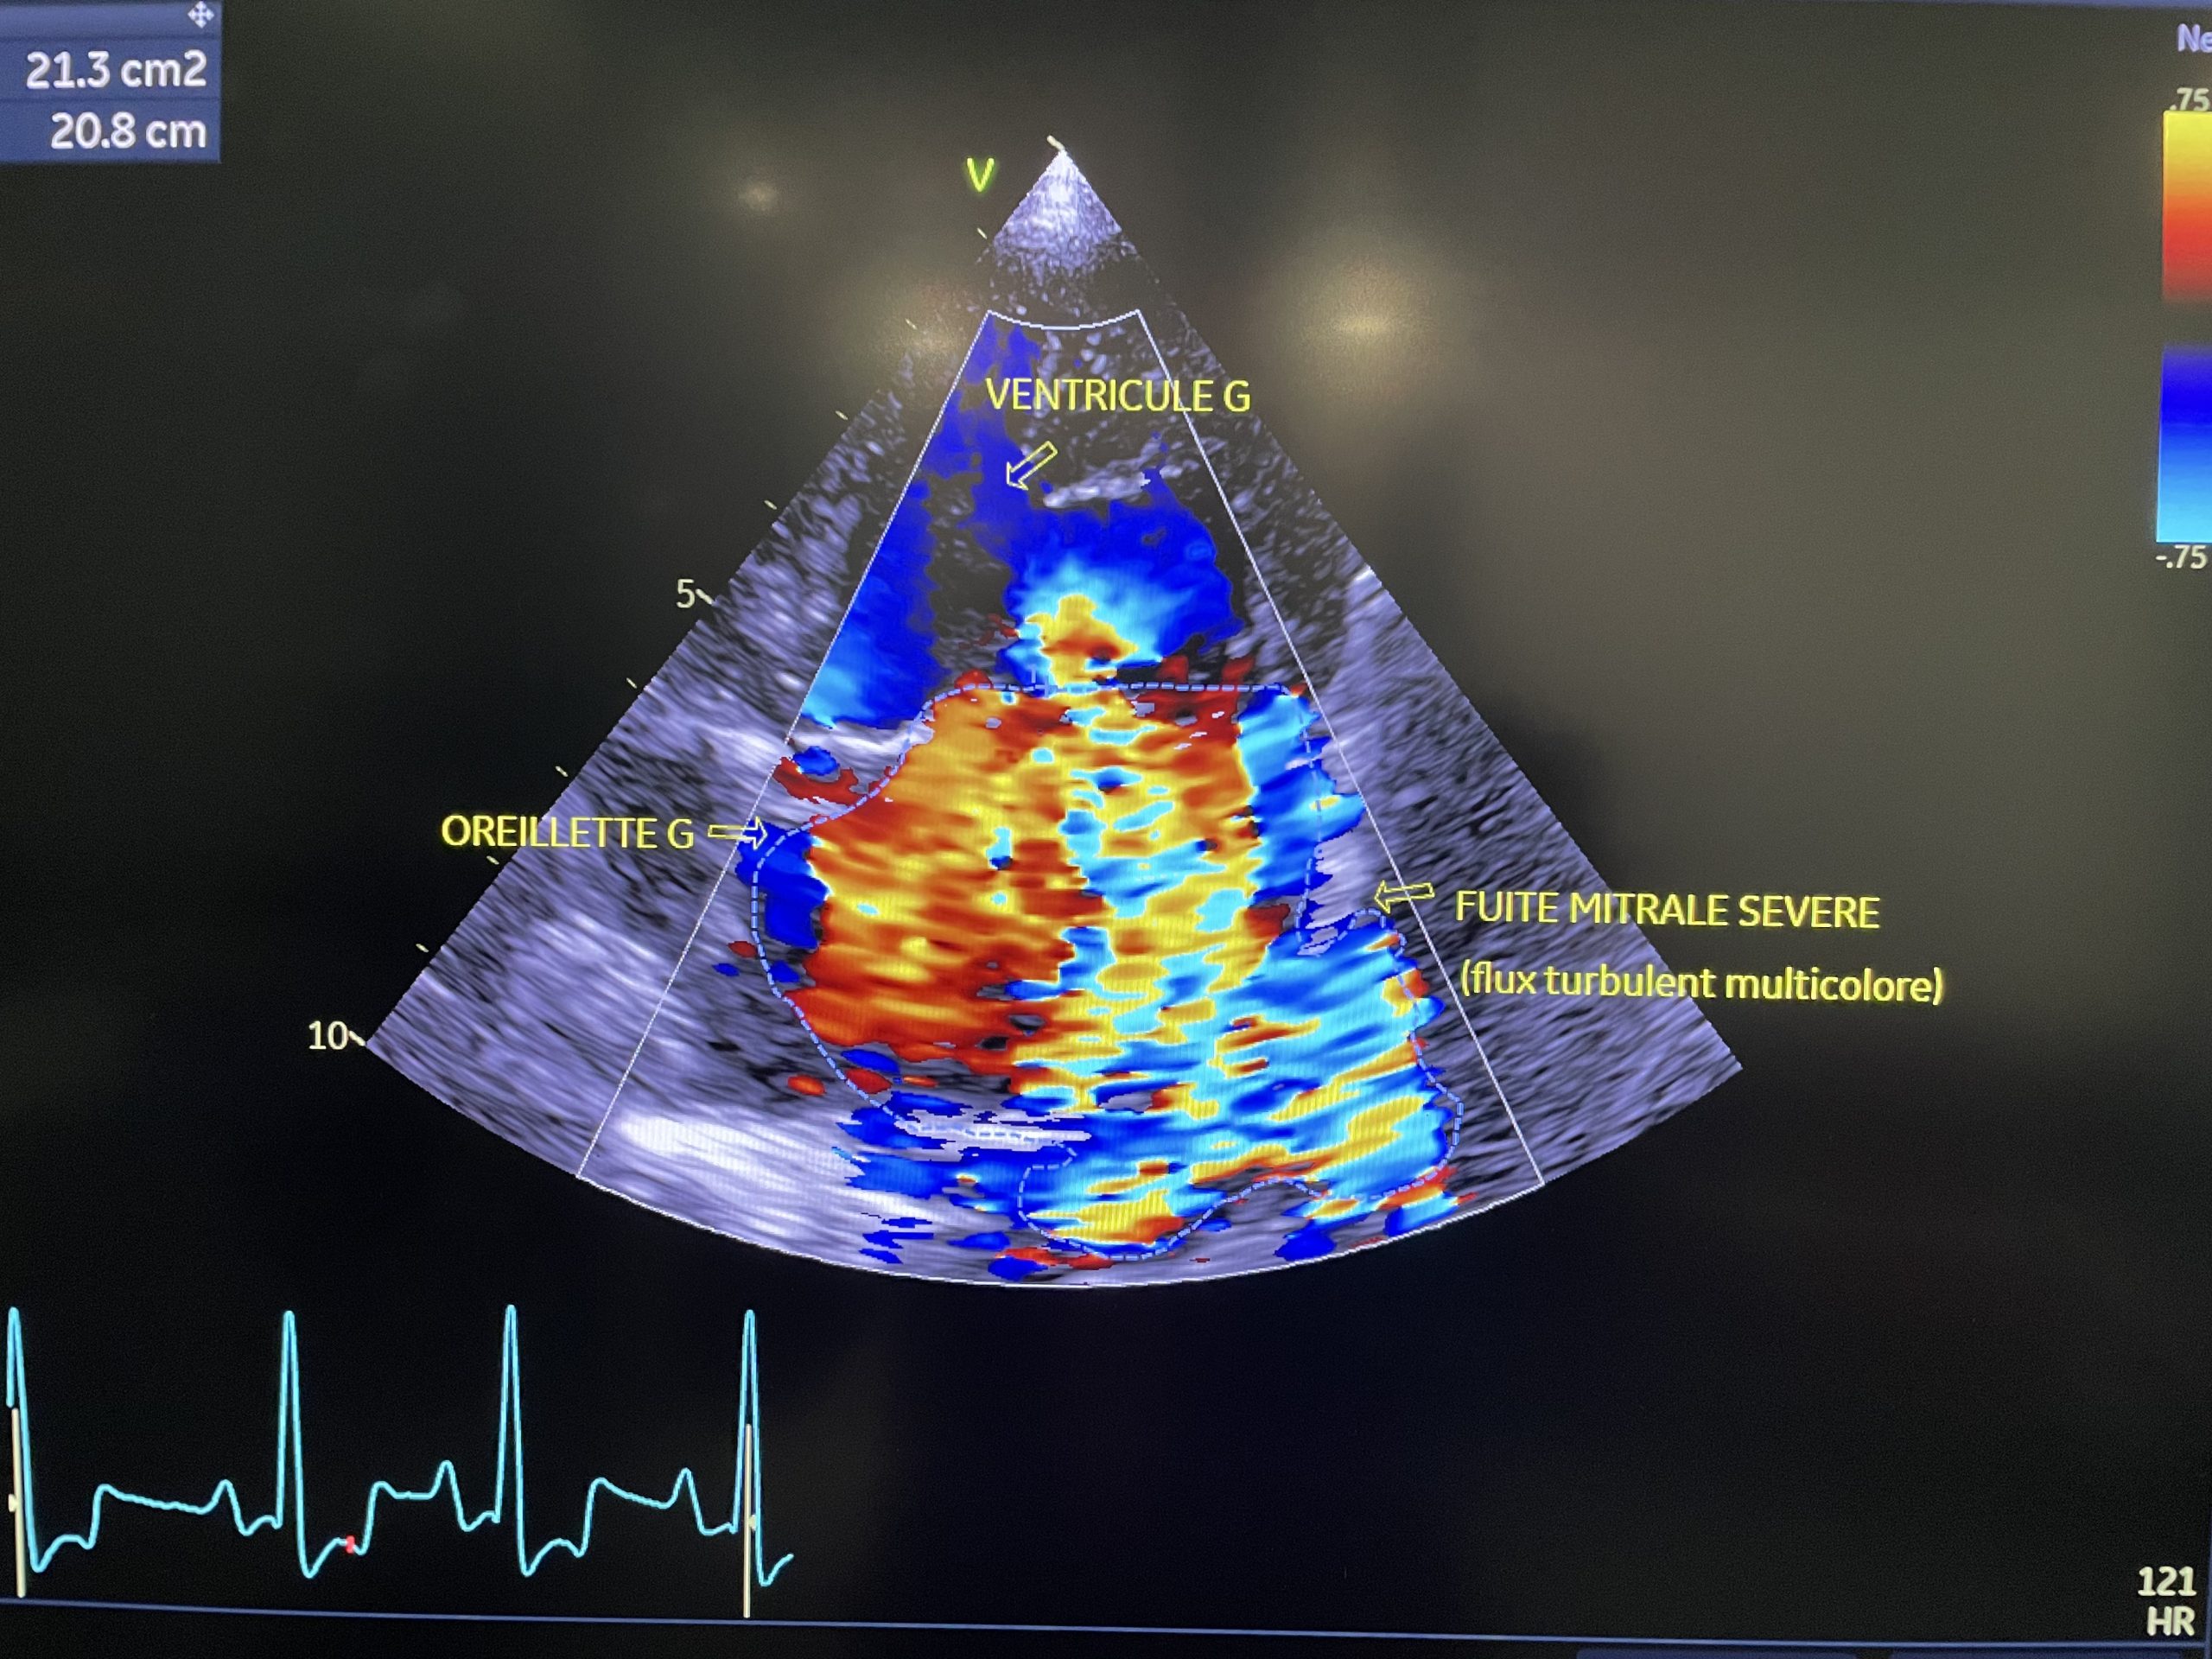

Le doppler vasculaire

Le doppler vasculaire (couleur ou spectral) est un examen qui permet d’explorer le flux sanguin dans les artères et les veines. Il a pour but de détecter la présence éventuelle d’un obstacle (par exemple, un caillot) qui empêcherait la bonne irrigation des organes.

Le mode doppler d’un échographe permet ainsi de connaître la direction des flux sanguins ainsi que leur vitesse et d’estimer par calcul les pressions qui règnent dans les cavités cardiaques.

Toutes ces informations sont indispensables au clinicien qui veut dresser un bilan complet des fonctions cardiaques ou de la qualité de l’irrigation des différents organes abdominaux.

La fonctionnalité de doppler vasculaire est intégrée à nos deux machines échographiques.